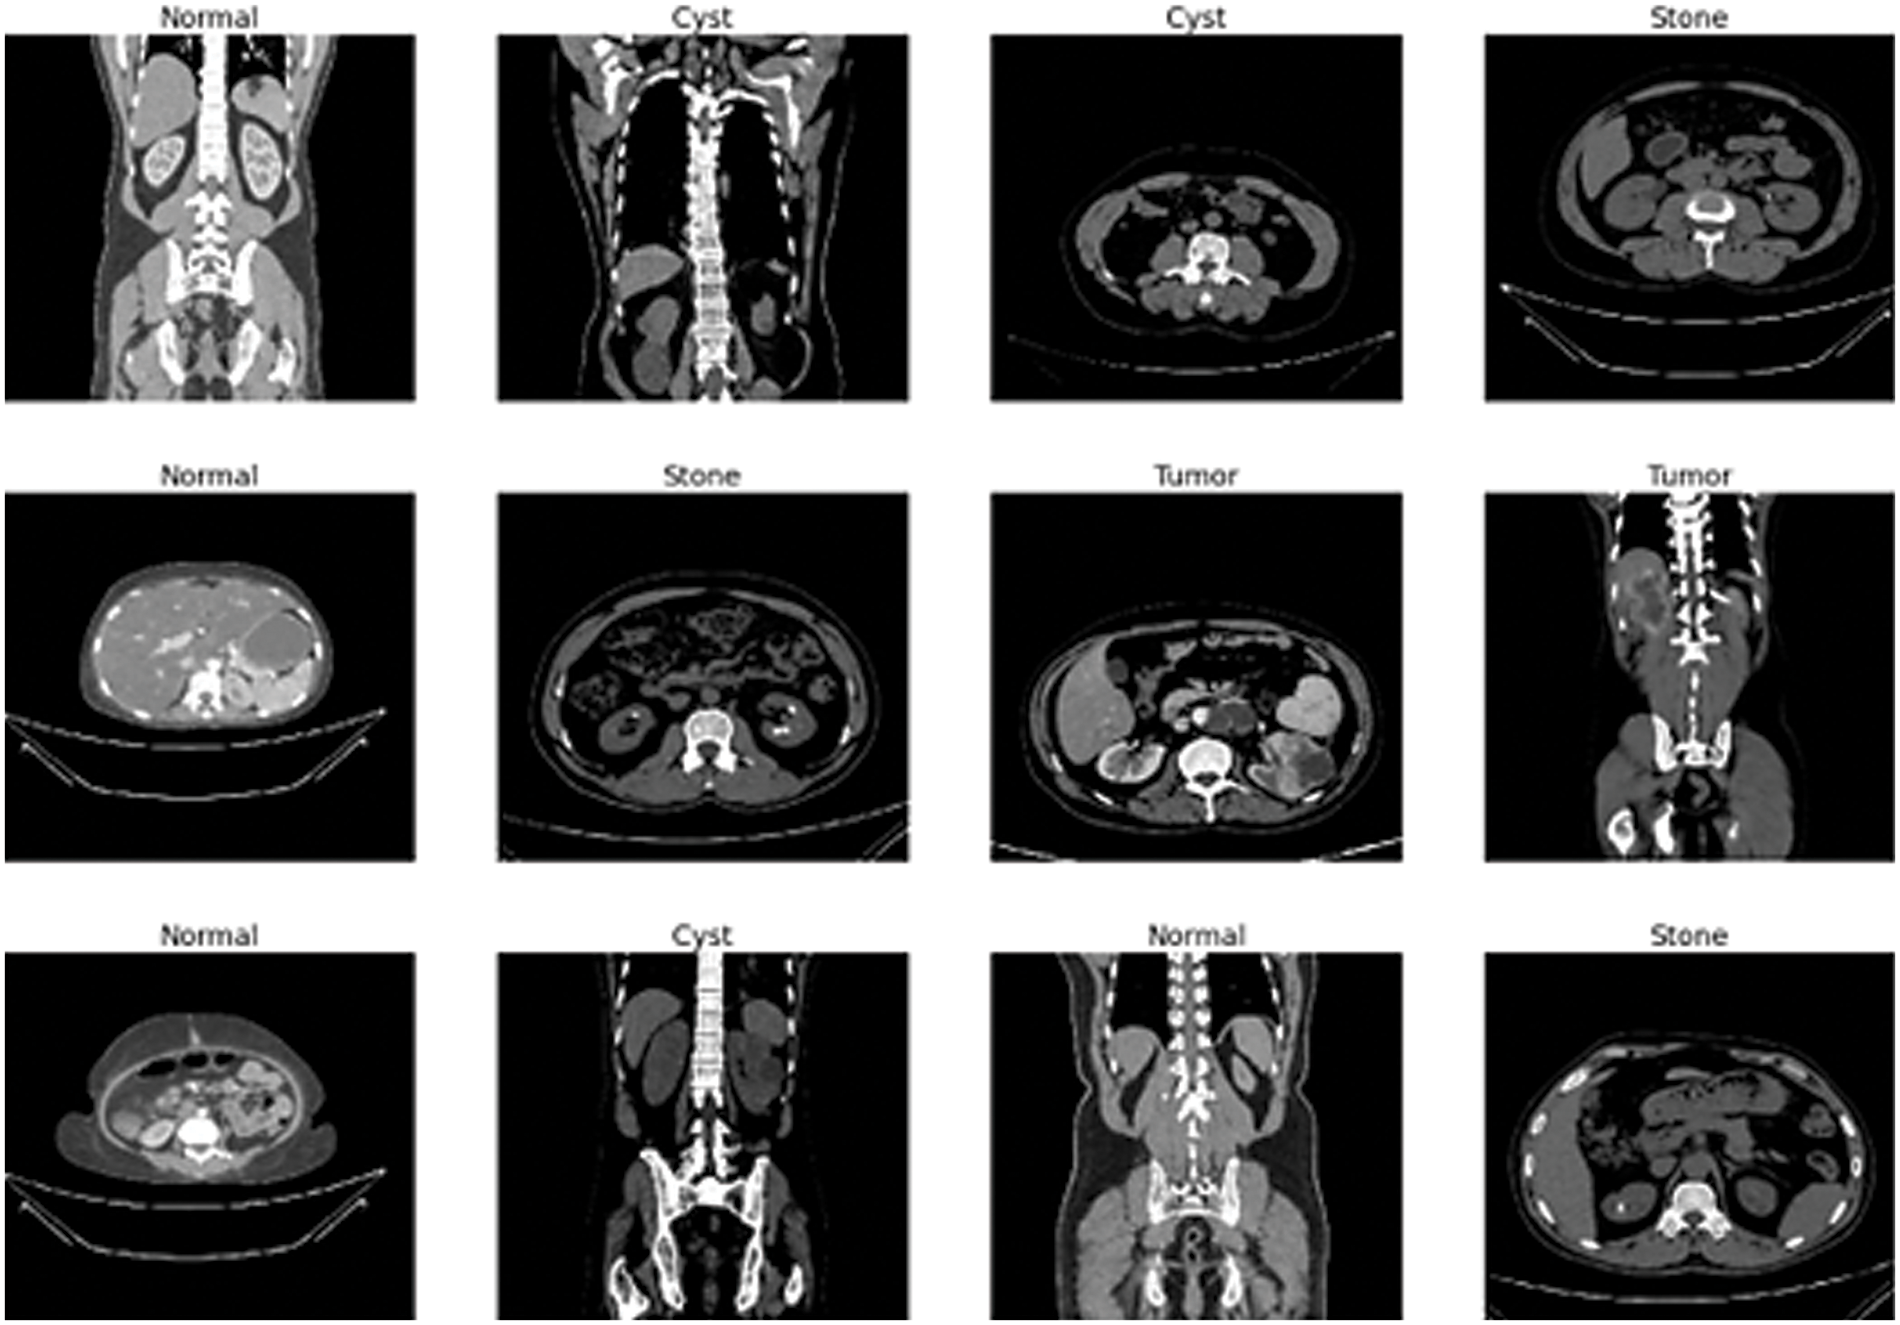

The data gathering and experimentation also adhere to all applicable protocols. The whole abdomen and urogram protocols follow for choosing the Coronal and Radial slices from chromatic and non-contrast studies. Then, researchers created a collection of images for every diagnostic finding from the carefully chosen Dicom study, one diagnosis at a time. The Dicom images are changed to a compact JPEG format after the researchers remove each patient's data and metadata. The Sante Dicom editor tool [55] converts data to jpg images. It is primarily used as a Dicom viewer with advanced features to help radiologists diagnose specific disease findings. The Philips IntelliSpace Portal 9.0 [56] application is used for data annotation and is an advanced image visualization tool for radiology images. A clinician and a medical consultant again verified each image finding to confirm the accuracy of the data after manual conversion and interpretation [57]. There are 12,446 unique data in the produced dataset, 3,709 of which are from cysts, 5,077 from normal data, 1,377 from stones, and 2,283 from tumors. Fig. 2 depicts a representative sampling of the datasets. The image shows the various sample of kidney scans such as stones, tumors, cysts and normal.

Figure 2: Sample data images of kidney tumor, cyst, normal, or stone results